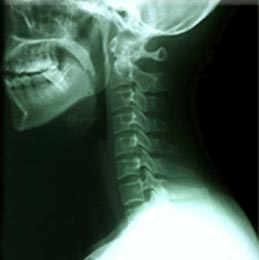

人體有七塊頸椎骨,它上承頭顱下接軀幹,神經血管交錯密集,可以說是全身的生命樞紐。頸椎非常脆弱,電腦操作者需要長時間低頭伏案,頸椎長時間處於緊張狀態,易慢性勞損、變形,產生骨質增生(又叫骨刺)、造成椎間盤突出,這種頸椎病變就是“電腦脖”,即頸椎病

“電腦脖”如果任其發展,病變的頸椎會壓迫人的頸部血管、神經和脊髓。壓迫血管,人會感到頭痛、頭暈,嚴重的會引發腦中風。壓迫神經,人會感到手臂酸脹、無力,時間長了,造成神經萎縮,失去知覺。壓迫脊髓,人會感到下肢發麻、發軟,嚴重的造成截癱。因此,得了頸椎病,一定要及早治療、積極治療,否則,就會嚴重影響正常活動,甚至危及生命。所以,一旦患上“電腦脖”一定要積極治療,防治“電腦脖”越早越好。